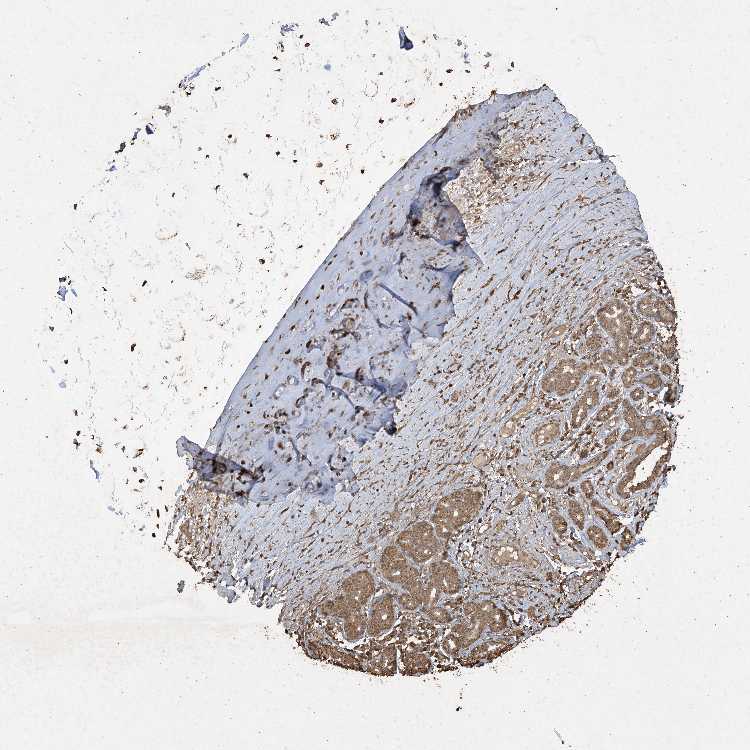

SULT2B1